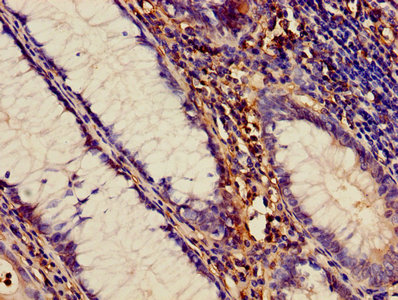

Immunohistochemistry of paraffin-embedded human colon cancer using CSB-PA001273LA01HU at dilution of 1:100